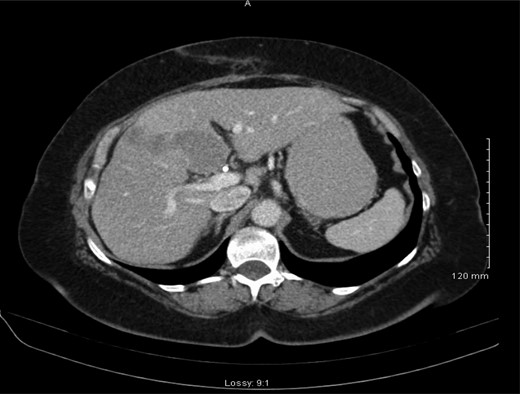

Histology demonstrated a 2.5 cm opaque stone and small cell undifferentiated carcinoma with tumour present in all layers of the gallbladder and lympho-vascular structures with invasion into the liver parenchyma. A subsequent staging computerized tomographic (CT) thorax, abdomen and pelvis demonstrated involvement of the lymph nodes within the coeliac axis and the porta hepatis, 3 mm nodular density in the right upper lobe of the lung and evidence of a metastatic deposit in the medial segment of the left hepatic lobe (Fig. 2). However, her completion staging CT brain revealed normal appearance.

Abdominal CT scan demonstrating metastasis to medial segment of left hepatic lobe.